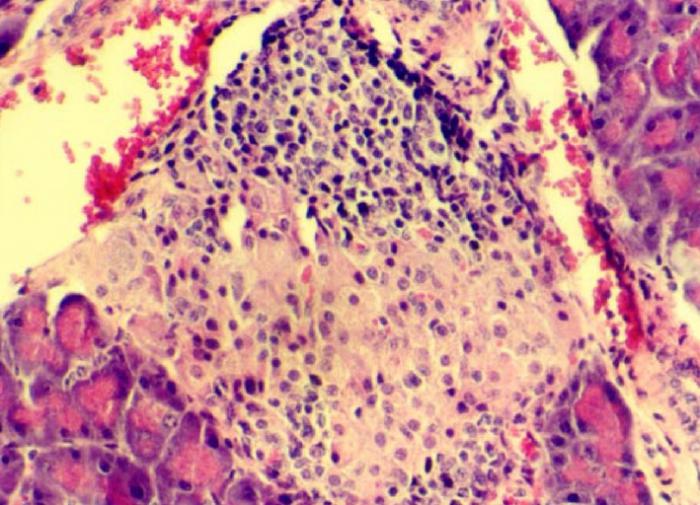

Исследования показали, что имплантация островковых клеток поджелудочной железы, которые способны вырабатывать инсулин по мере необходимости, может освободить пациентов с диабетом от необходимости регулярных инъекций. Однако прежние подходы к этой технике столкнулись с проблемой нехватки кислорода для клеток внутри импланта.